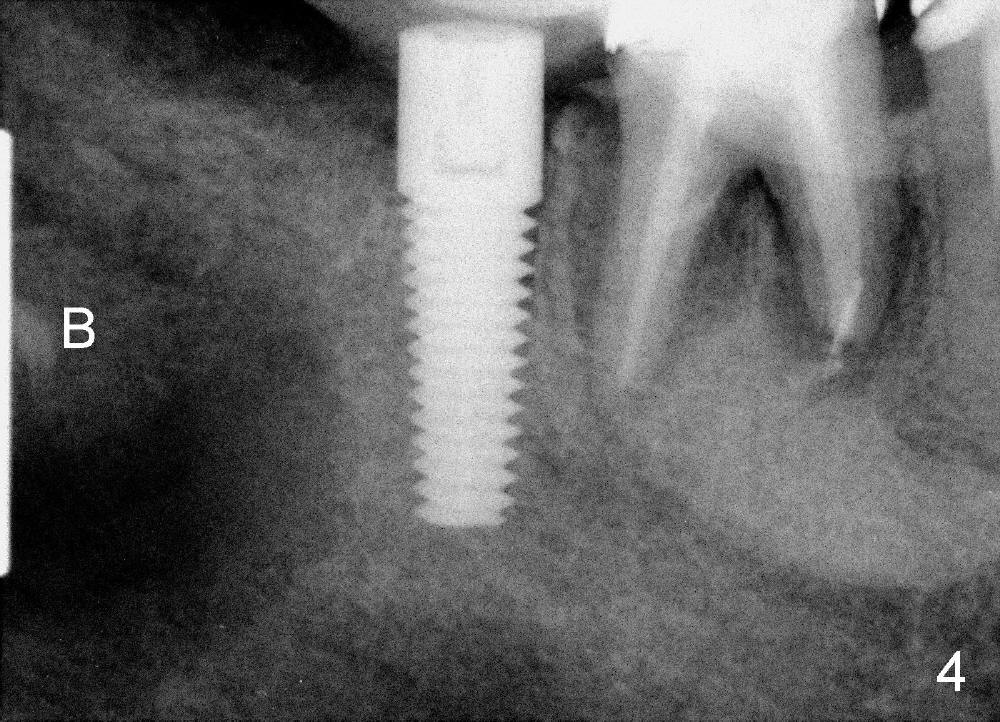

A 5x17 mm implant is placed (Fig.3).  When the gauze is removed, copious hemorrhage resumes, which is stopped by pressing into the defect with mixture of autogenous bone (harvested from osteotomy in the mesial socket of the 2nd molar) and 3.5 g of allograft (Fig.4: B).